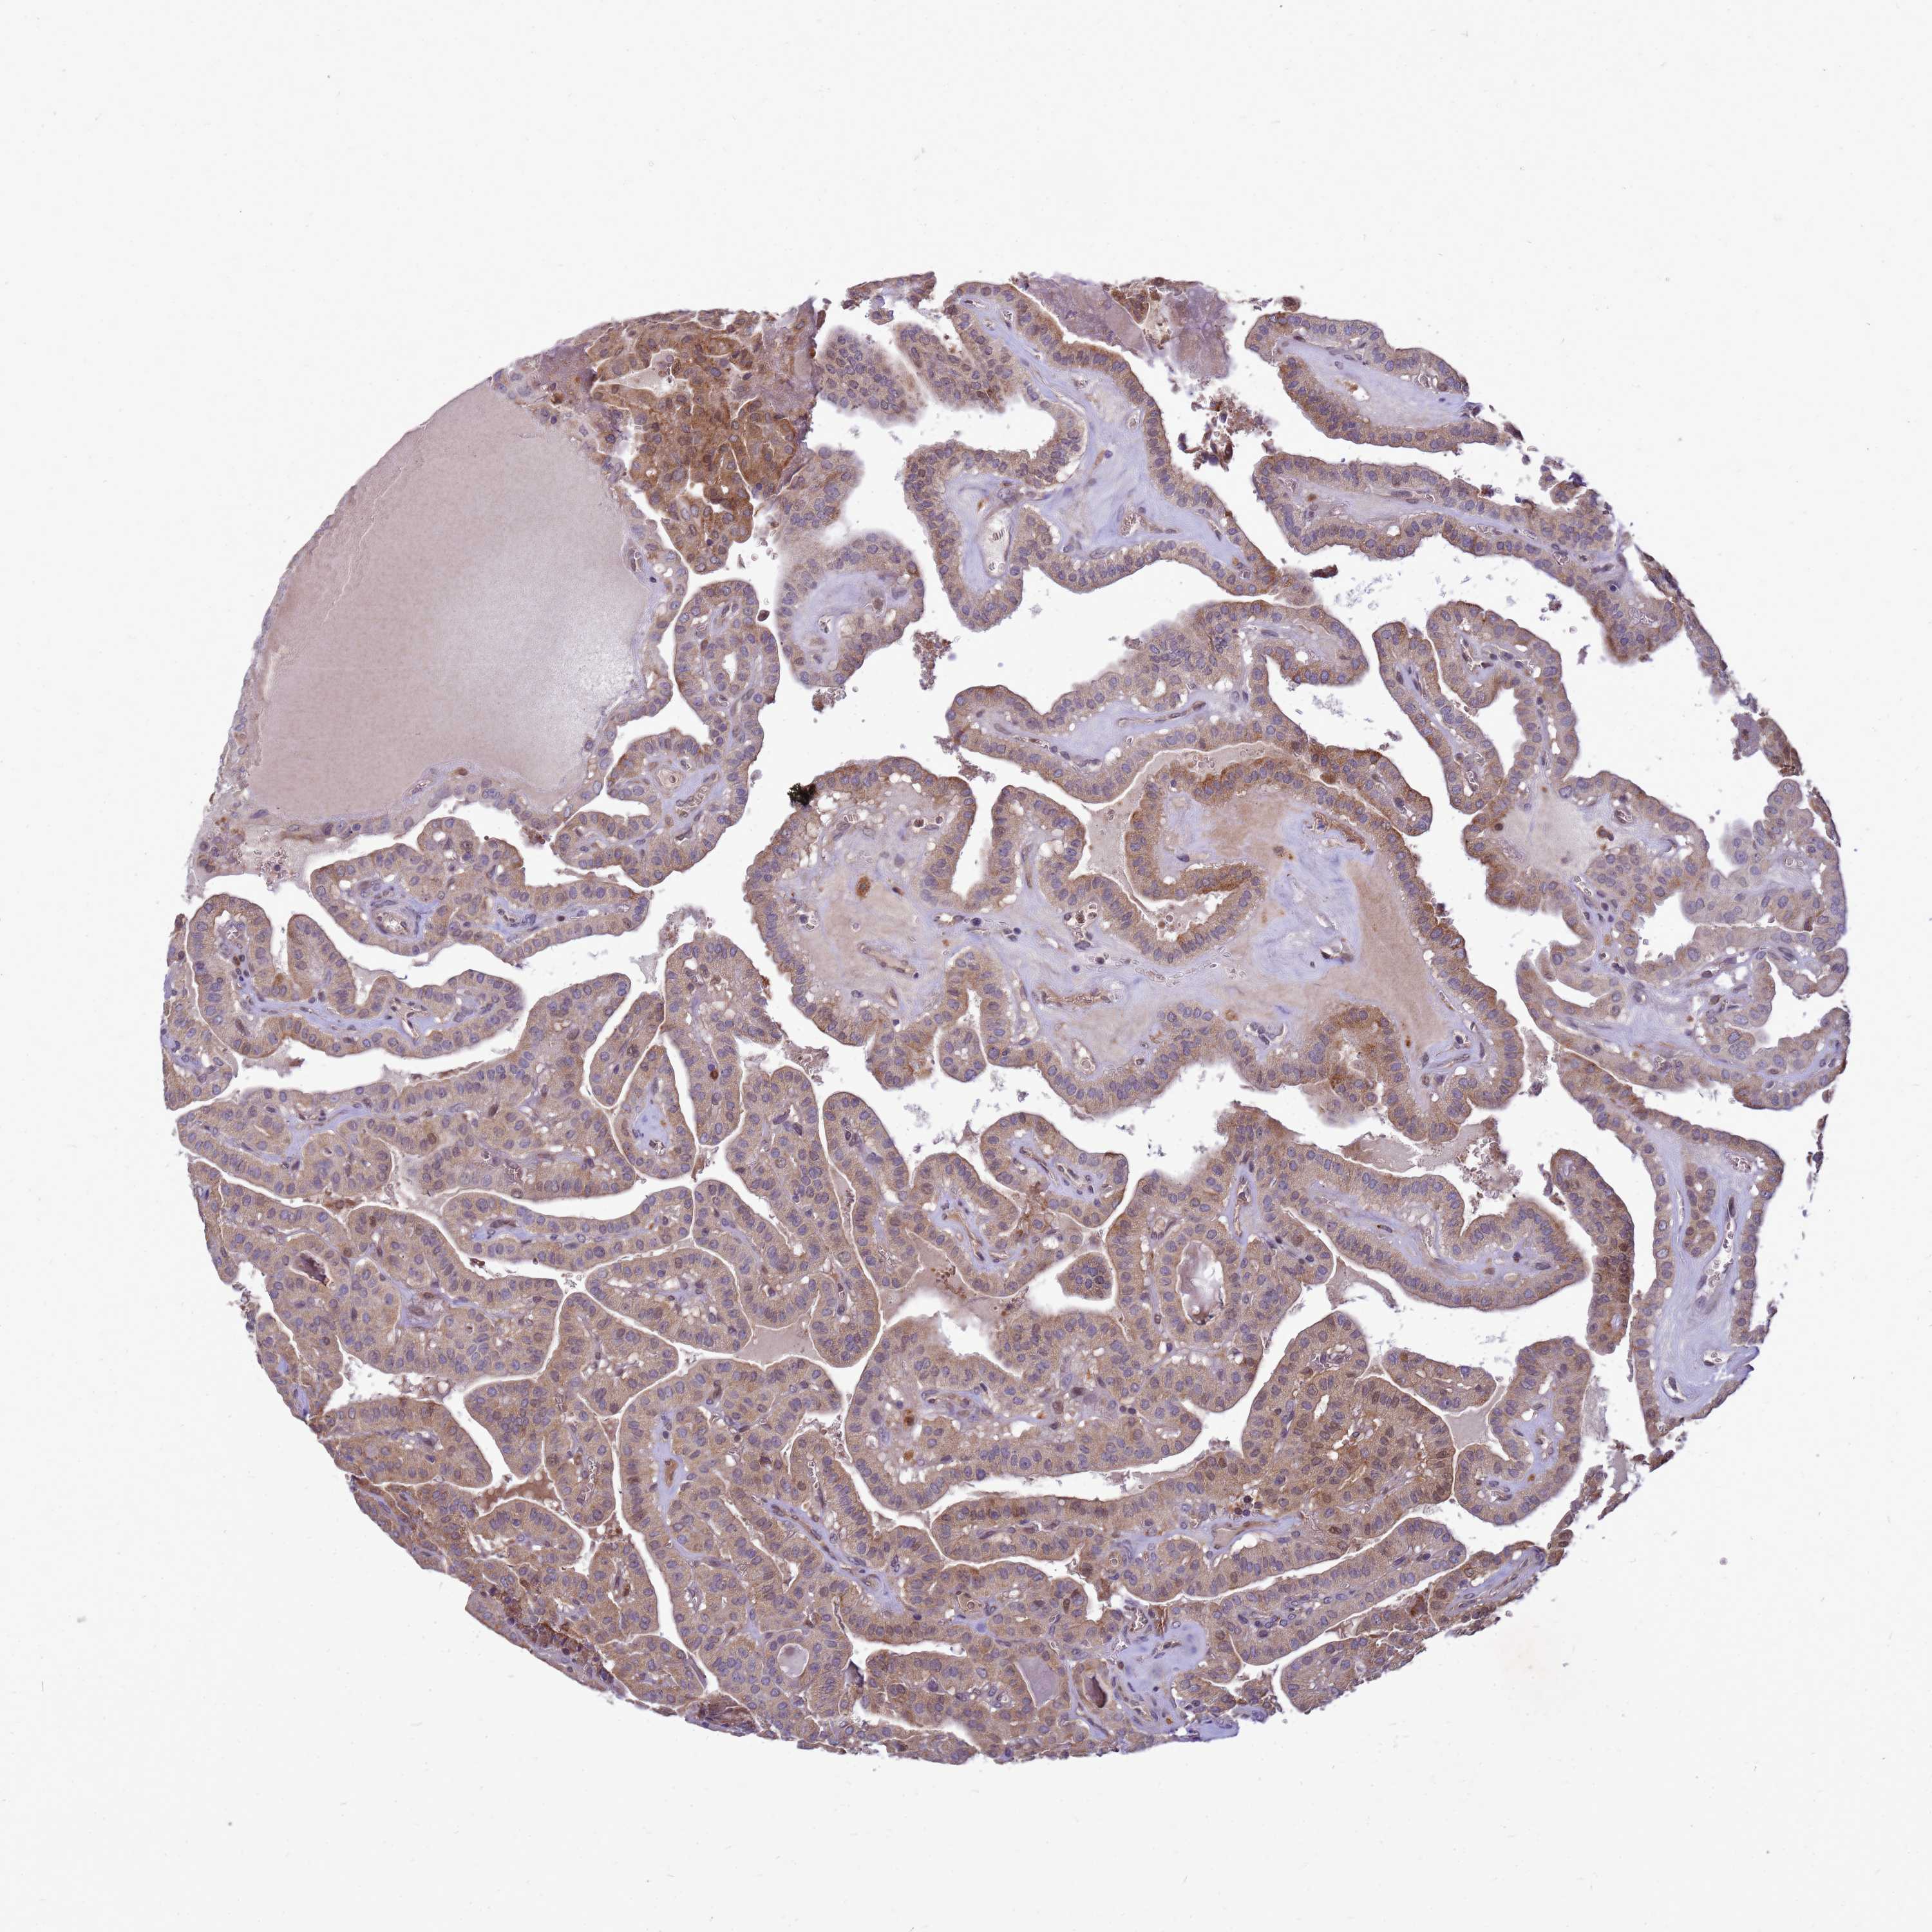

THYROID CANCER - Protein expressioni

A mouse-over function shows sample information and annotation data. Click on an image to view it in a full screen mode. Samples can be filtered based on level of antibody staining by selecting one or several of the following categories: high, medium, low and not detected. The assay and annotation is described here.

Note that samples used for immunohistochemistry by the Human Protein Atlas do not correspond to samples in the TCGA dataset.

Antibody stainingi

Antibody staining in the annotated cell types in the current human tissue is reported as not detected, low, medium, or high, based on conventional immunohistochemistry profiling in selected tissues. This score is based on the combination of the staining intensity and fraction of stained cells.

Each image is clickable and will lead to virtual microscopy that enables deeper exploration of all samples and also displays staining intensity scores, fraction scores and subcellular localization as well as patient and tissue information for each sample.

Antibody HPA045537

Papillary adenocarcinoma, NOS

Follicular adenoma carcinoma, NOS